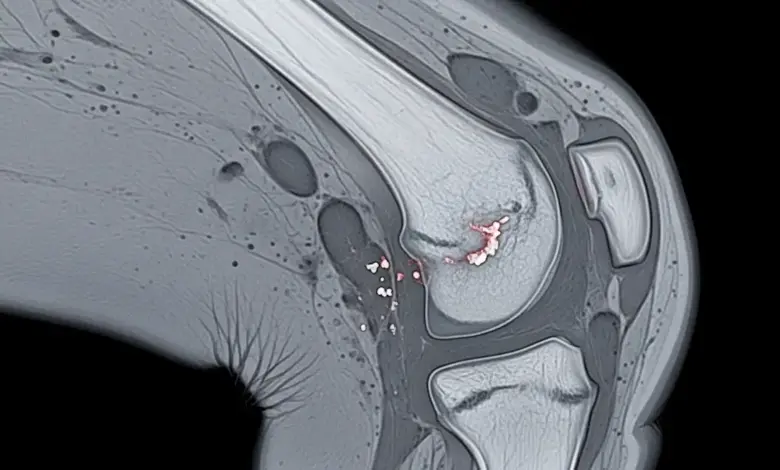

A radiografia pode mostrar calcificações e irregularidades ósseas. O ultrassom pode avaliar a inserção do tendão. A ressonância costuma ser útil quando o quadro é mais persistente, quando existe suspeita de lesão associada ou quando se busca uma leitura mais detalhada do tecido.

No joelho, o laudo pode mencionar entesopatia degenerativa na inserção do tendão patelar, no polo inferior da patela, na tuberosidade da tíbia ou em outras áreas sujeitas à tração repetitiva.

Quando o tecido já está sofrendo há algum tempo, a dor passa a ser mais frequente e o exame de imagem começa a mostrar sinais desse desgaste, aumentando o risco de tendinopatia patelar.